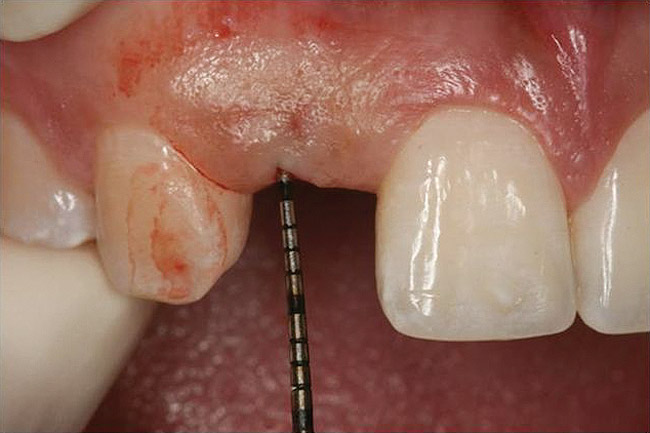

Figure 10  Clinical examination of the bound edentulous space: Measurement of the distal (Fig 10) and mesial (Fig 11) interproximal tissue height using a periodontal probe supplements data obtained from the periapical radiograph. Estimation of the buccal tissue thickness (bone sounding) is performed at the determined location of the gingival zenith using a guide developed from the diagnostic waxing (Fig 12).

Figure 10

Figure 11   Clinical examination of the bound edentulous space: Measurement of the distal (Fig 10) and mesial (Fig 11) interproximal tissue height using a periodontal probe supplements data obtained from the periapical radiograph. Estimation of the buccal tissue thickness (bone sounding) is performed at the determined location of the gingival zenith using a guide developed from the diagnostic waxing (Fig 12).

Figure 11

Figure 12   Clinical examination of the bound edentulous space: Measurement of the distal (Fig 10) and mesial (Fig 11) interproximal tissue height using a periodontal probe supplements data obtained from the periapical radiograph. Estimation of the buccal tissue thickness (bone sounding) is performed at the determined location of the gingival zenith using a guide developed from the diagnostic waxing (Fig 12).

Figure 12